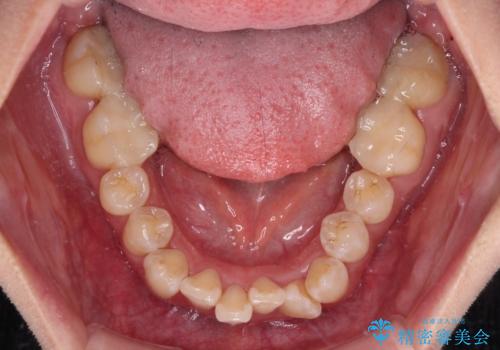

- 前歯1本が後ろ側に隠れてしまうほどのデコボコを気にして来院された患者様です。

前歯のデコボコが顕著なのはもちろんですが、左右ともに奥歯の咬み合わせに問題があり、上顎臼歯が前方位にある状態でした。

上顎は左右の第一小臼歯2本を、下顎は左右第二小臼歯2本を抜歯することで、奥歯の咬み合わせを改善しながら、デコボコを解消していくこととしました。